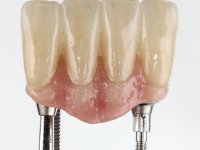

Faced with two possibilities, try to use the implant or remove it, I chose to remove it. Two reasons for this decision, first, the buccal bone loss was very extensive and second, the adjacent teeth had a poor prognosis in the medium term. In this sense, it was proposed to remove the implant, extract teeth 42 and 32, simultaneously place 2 implants in their place and immediately rehabilitate the area with a 4-piece screw-retained temporary bridge. After osseointegration, a 4-element screw-retained bridge would be made with ceramic in a coronal and gingival shade.

After an imaging study, the placement of two implants of 3.3 mm in diameter and 10 mm in length was planned. On the day of surgery, teeth 42 and 32 were extracted and the implant was removed. The implants were placed in the area of the alveoli, taking care to slightly lingualize their positioning. An impression was made using the open tray technique with the flap open for the fabrication of the immediate provisional bridge. While the impression was taken to the laboratory, tall healing screws were placed and the surgical wound was sutured. The patient waited 2 hours in the waiting room while the temporary bridge was made in the laboratory. An immediate screw-retained provisional bridge was placed and its seating was controlled by imaging. After 3 months, the final impression was made using an open tray technique. In this consultation, we took the opportunity to polish the temporary bridge with rubber cups so that the soft tissues could mature in better conditions. Information was collected to better characterize the monolithic structure in Zr. Color guides were used for the coronal and gingival ceramics. In the laboratory, a bridge was made in Zr. bolt-on that has been carefully characterized. After approval by the patient, it was definitively placed in the mouth. Tightening was performed with a dynamic wrench with a torque of 35 N. The holes were covered with Teflon and filled with composite resin.